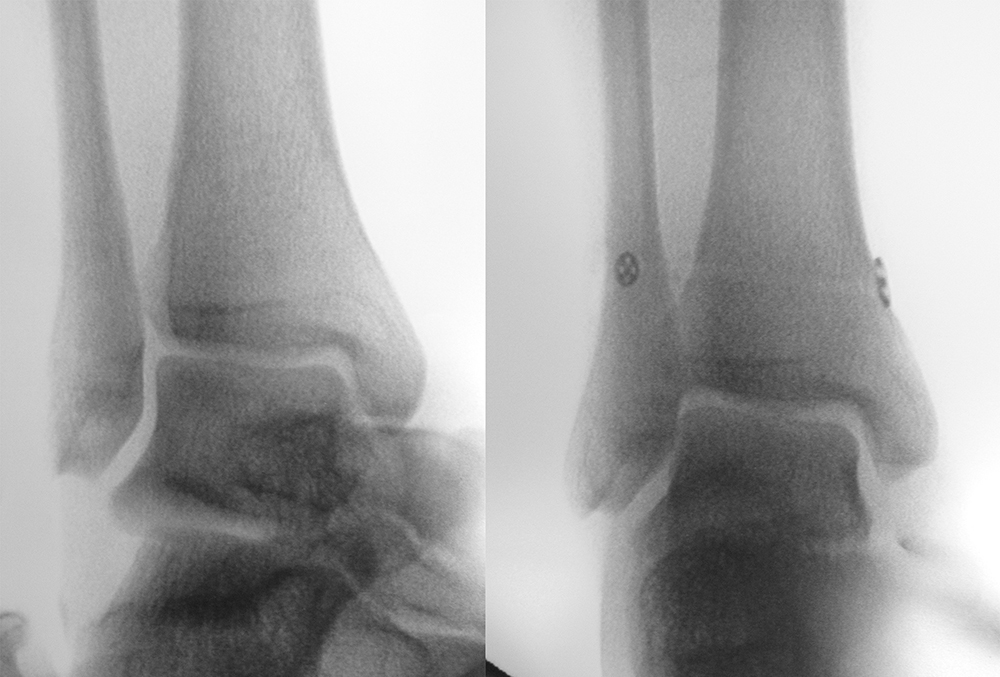

Röntgenaufnahmen dienen primär dem Ausschluss einer knöchernen Verletzung. Die Beurteilung der Geometrie der Malleolengabel kann einen ersten Hinweis auf eine Syndesmosenverletzung liefern. Die notwendigen Röntgenaufnahmen umfassen das Sprunggelenk anterior-posterior, lateral und in 20° Innenrotation (Mortise view). Zur Beurteilung der Syndesmose sind verschieden Parameter in der Mortise view beschrieben. Zu diesen zählen der tibiofibulare Clearspace, der mediale Clearspace, sowie die Überlappung der distalen Fibula und Tibia im Bereich der Incisura (Abbildung 2). Der Tibiofibulare Clearspace wird als verlässlichster Indikator für eine Syndesmosenverletzung gesehen, da er nicht signifikant von der tibialen Rotation beeinflusst wird 32. Er wird 1 cm proximal des Tibiaplafonds gemessen und sollte weniger als 6mm betragen 33. Jede Messung, die diesen Wert übersteigt, stellt einen Hinweis für eine Syndesmosenverletzung dar. Eine tibiofibulare Überlappung von 6 mm oder mehr in der AP Aufnahme, sowie mehr als 1 mm in der Mortise View Aufnahme gelten als physiologisch 33. Der mediale Clearspace sollte nicht mehr als 4 mm betragen 34.

Abbildung 3 zeigt ein Sprunggelenk nach Syndesmosenverletzung mit einem erweiterten Tibiofibularen Clearspace.